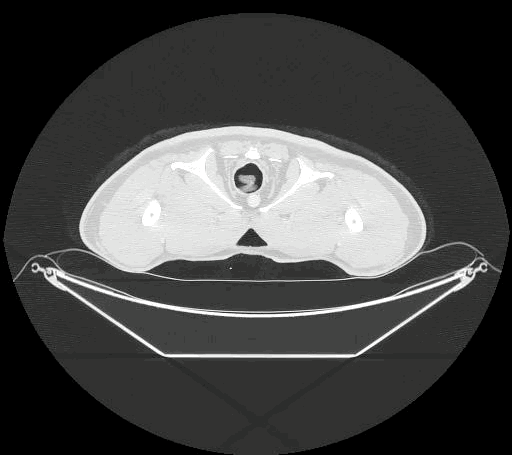

然而,当研究者抓起一只袋熊,用 CT 扫描它的屁股时,却发现它的肛门明明就很圆啊!和其他拉圆屎的动物没什么两样!而且影像中能看到:袋熊的骨盆骨骼距离大肠很远,没可能帮助挤压粪便。

袋熊屁股扫描影像 图源:hu.gatech.edu